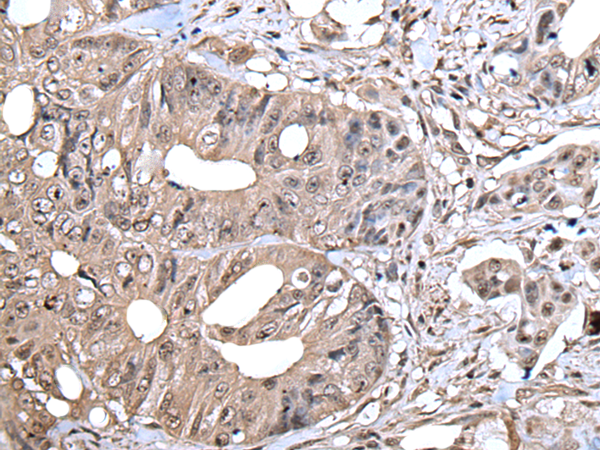

IHC positive control: |

Human colorectal cancer |